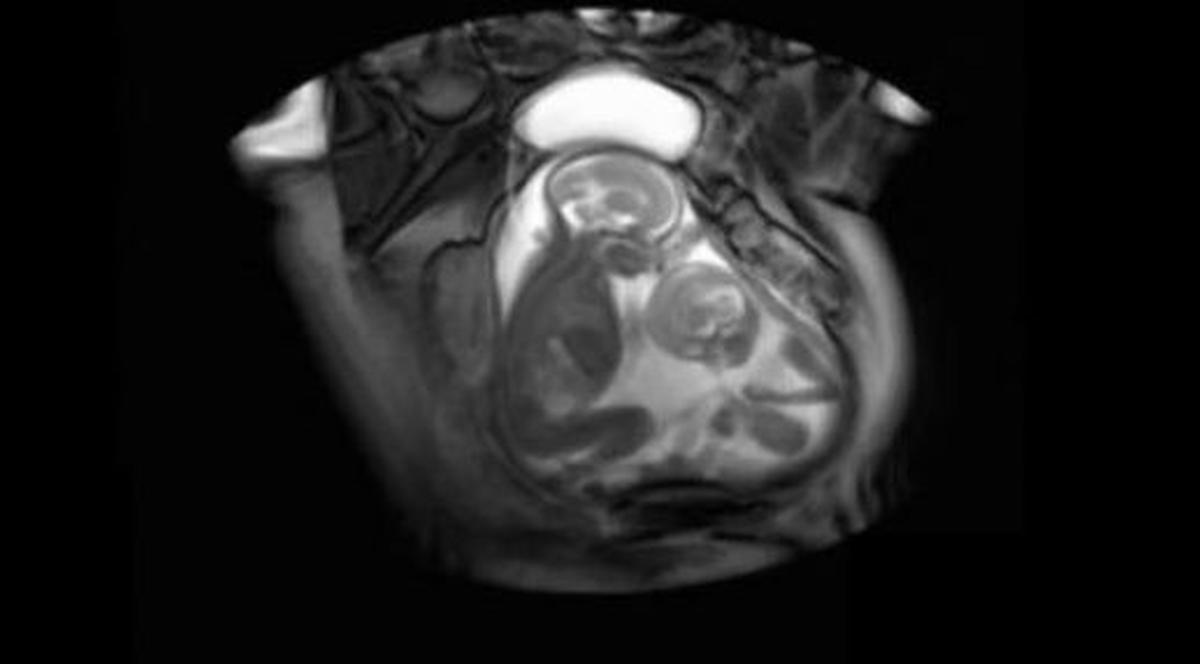

Imaginile arată că lupta pentru supravieţuire începe încă din uterul mamei şi continuă de îndată ce micuţii vin pe lume. Cum ţi se pare înregistrarea?

Top 3 lucruri inedite despre gemeni:

-Şanse să aveţi gemeni identici sunt: 4 la 1000, iar gemeni fraternali sunt: 12 la 1000

-Gemenii sunt mai frecvenţi la afro-americani si foarte rari la asiatici

-Mai mult de jumatate din gemeni sunt bărbaţi